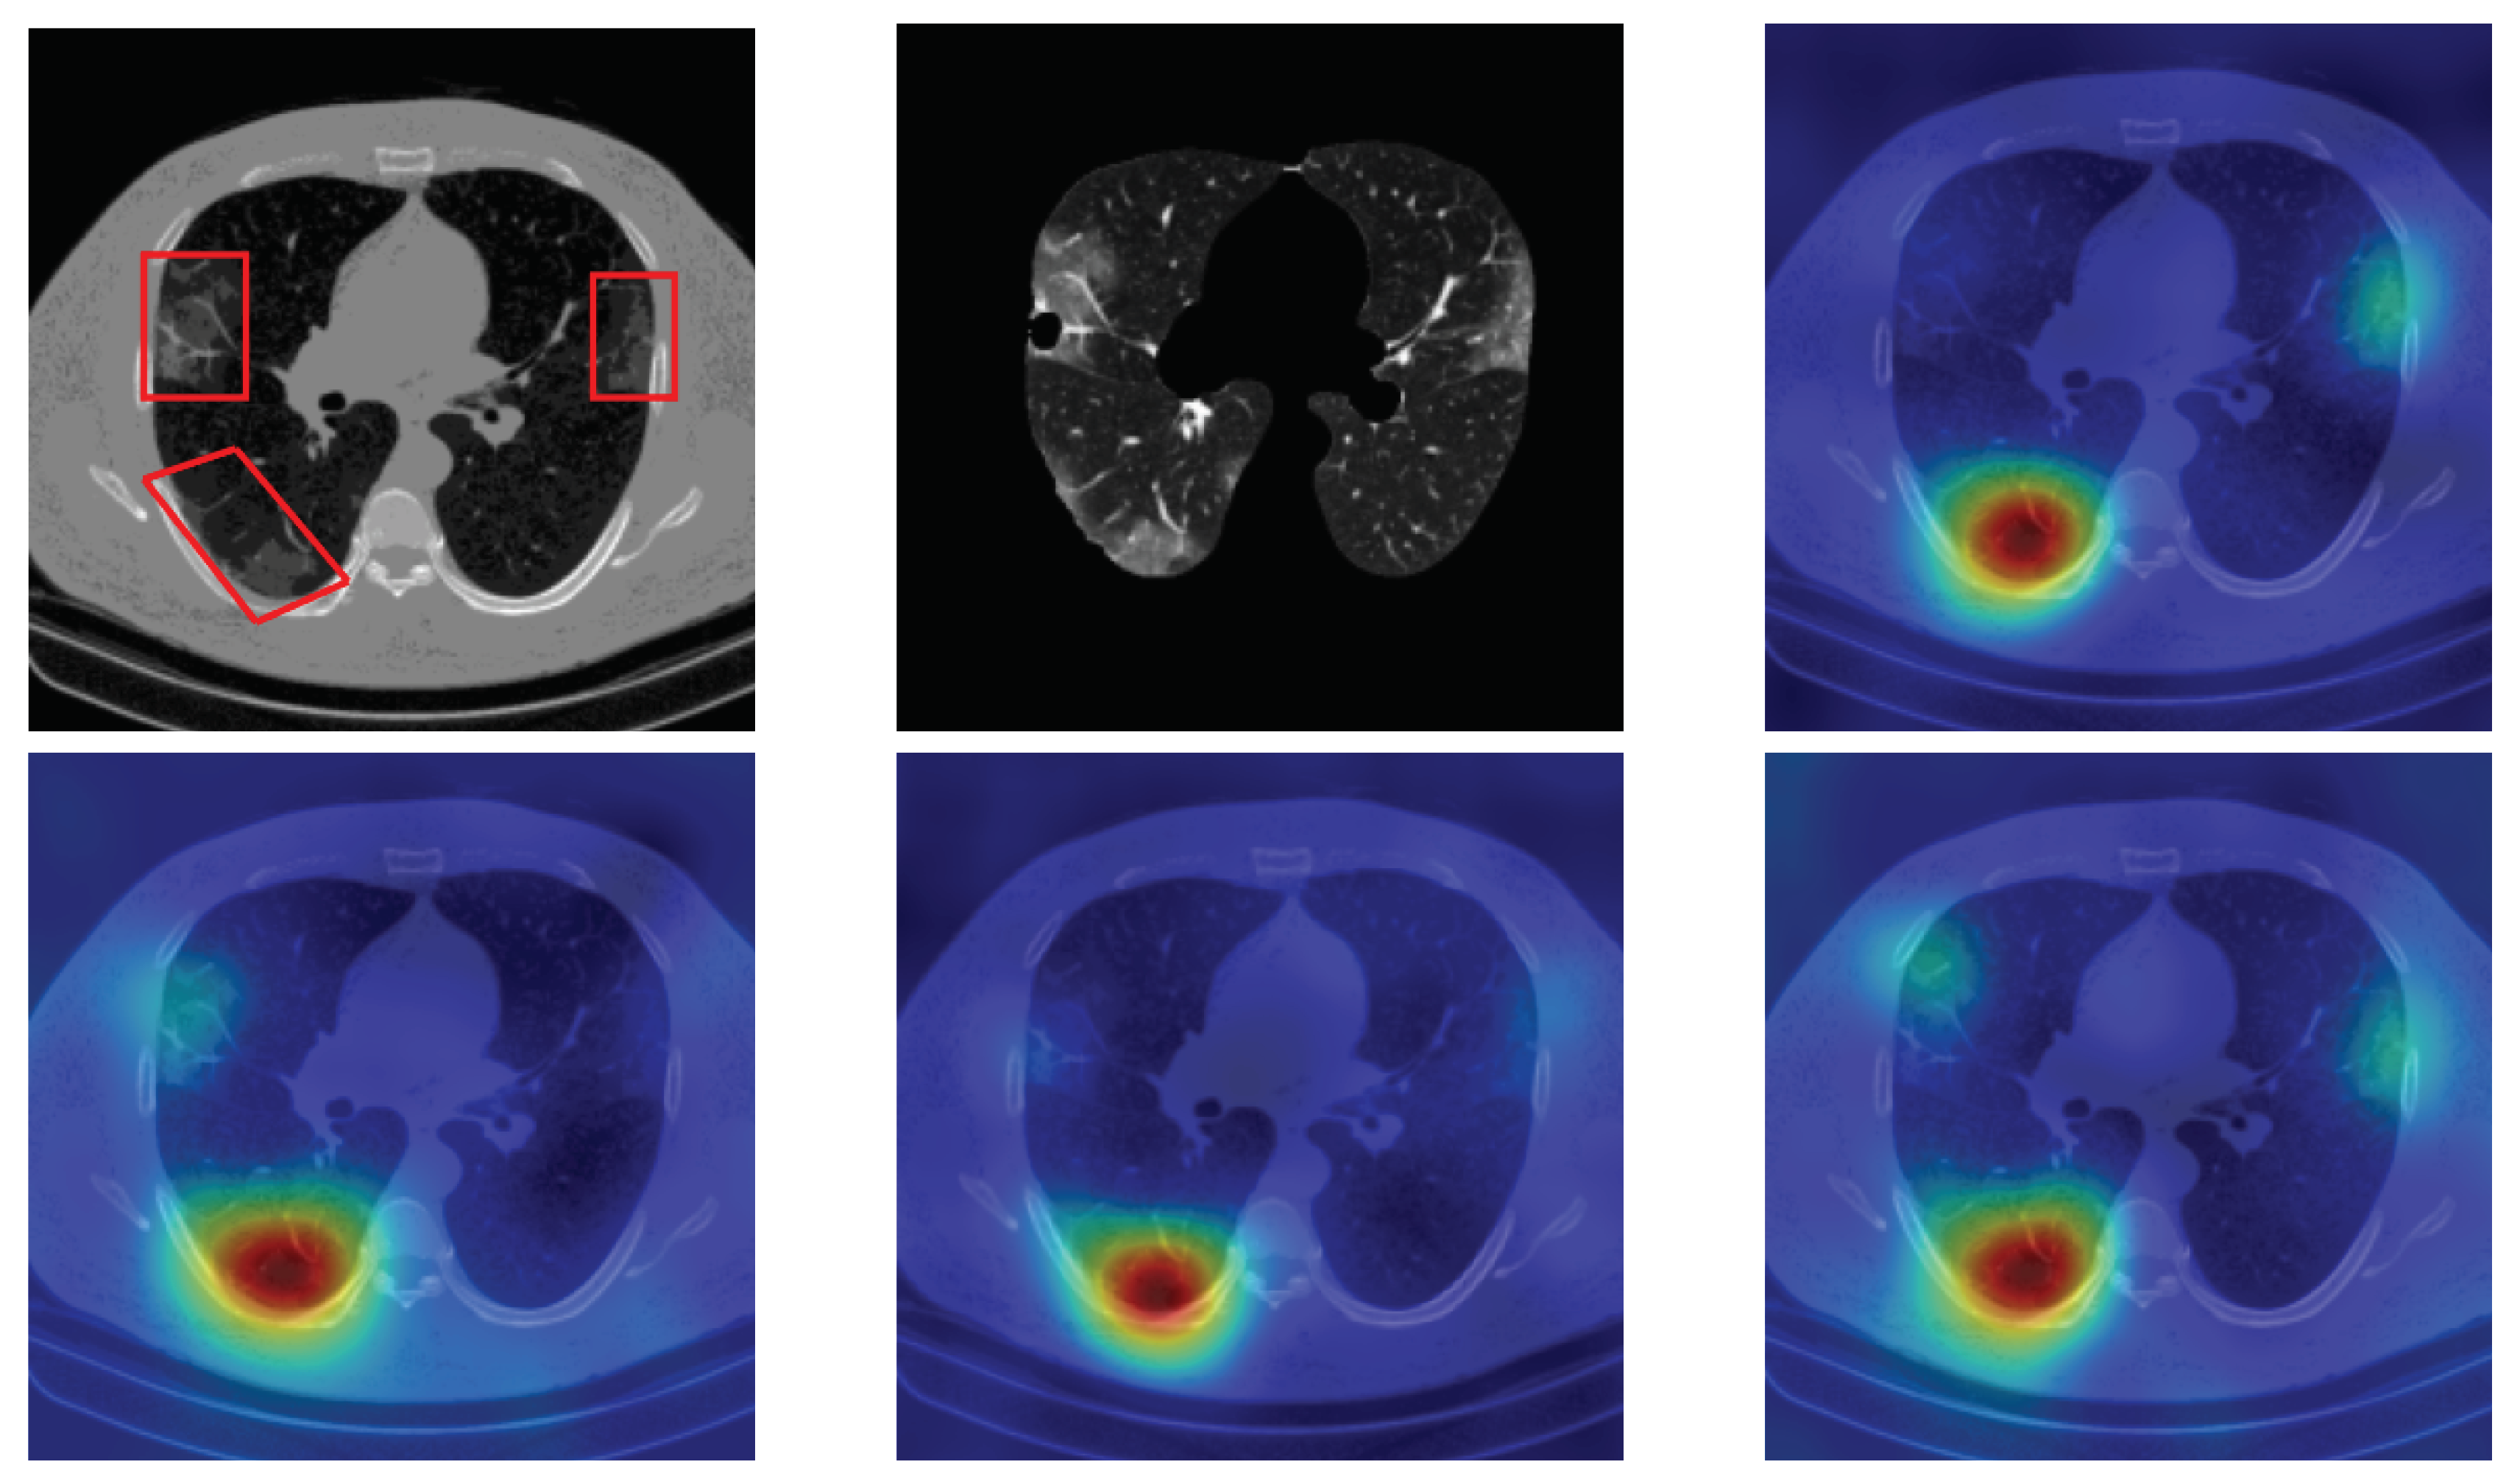

4.5. Heat Map

To have more intuition about the most important lung regions that the CNN architectures consider to classify the slice images, we used the randomized input sampling for explanations (RISE) approach [37]. Figure 13, Figure 14 and Figure 15 consist of two heat map examples of COVID-19, Cap, and normal cases, respectively. In the first example from Figure 13, we notice that despite the lung segmentation being not fully correct (it misses a considerable part of the infected region), the four CNN architectures gave more importance to the infected regions and to the lung regions in general. In the second example from Figure 13, we observe that the lung lobes were precisely segmented, and the heat maps of the four CNN architectures were well defined the infected regions, especially the Wide-Resnet-50 architecture. From both Cap examples in Figure 14, we notice that despite the lung segmentation missing considerable infected parts as well as the lung lobe regions, the heat maps of all CNN architectures give more importance to the infected region and to the lung lobes in general. This proves that the trained CNN architecture is able to define the regions of interest even when the lung lobes segmentation is not good. For the normal slice examples in Figure 15, the trained CNN architectures gave more importance to the lung lobes, especially the lower region, since the infection usually occurs there. The heat maps of COVID-19, Cap, and normal cases prove that the CNN architectures learned precisely where to look to identify the infection from the slice images.

Figure 13.

RISE heat map examples of COVID-19 slice images using the trained multi-tasks CNN architectures (ResneXt-50, Densenet-161, Inception-v3, and Wide-Resnet-50). The first example is shown in the first two rows, where the images represent the input slice image and segmented lung lobes results, followed by the heat maps of ResneXt-50, Densenet-161, Inception-v3, and Wide-Resnet-50, respectively. The second example is in rows 3 and 4.